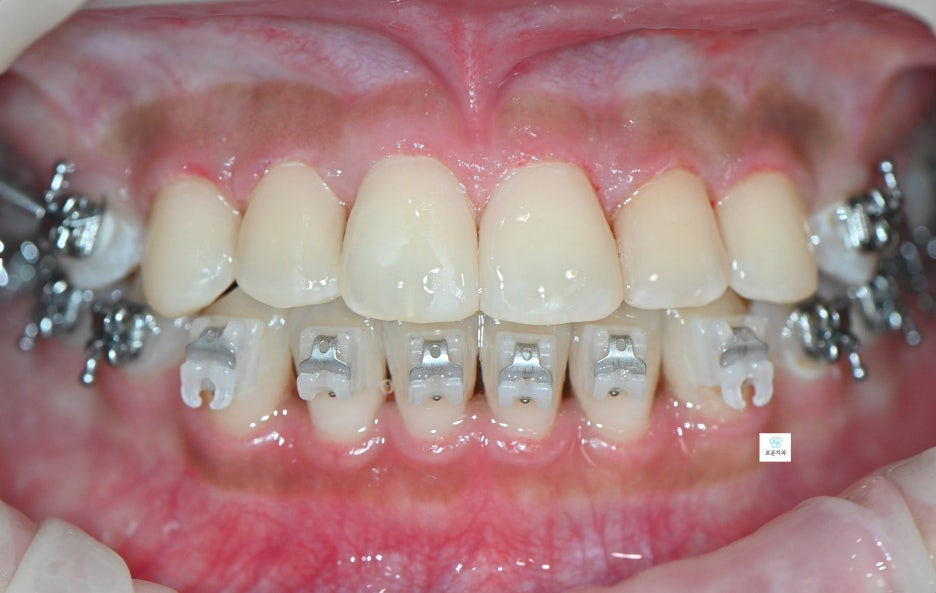

엑스레이 촬영 결과

인접면 충치가 더욱 명확하게 확인되었으며

깊이에 따라 마취 후 치료를 진행했습니다.

충치 부위를 제거한 뒤

자연스러운 색상의 레진으로

깔끔하게 수복하였습니다.